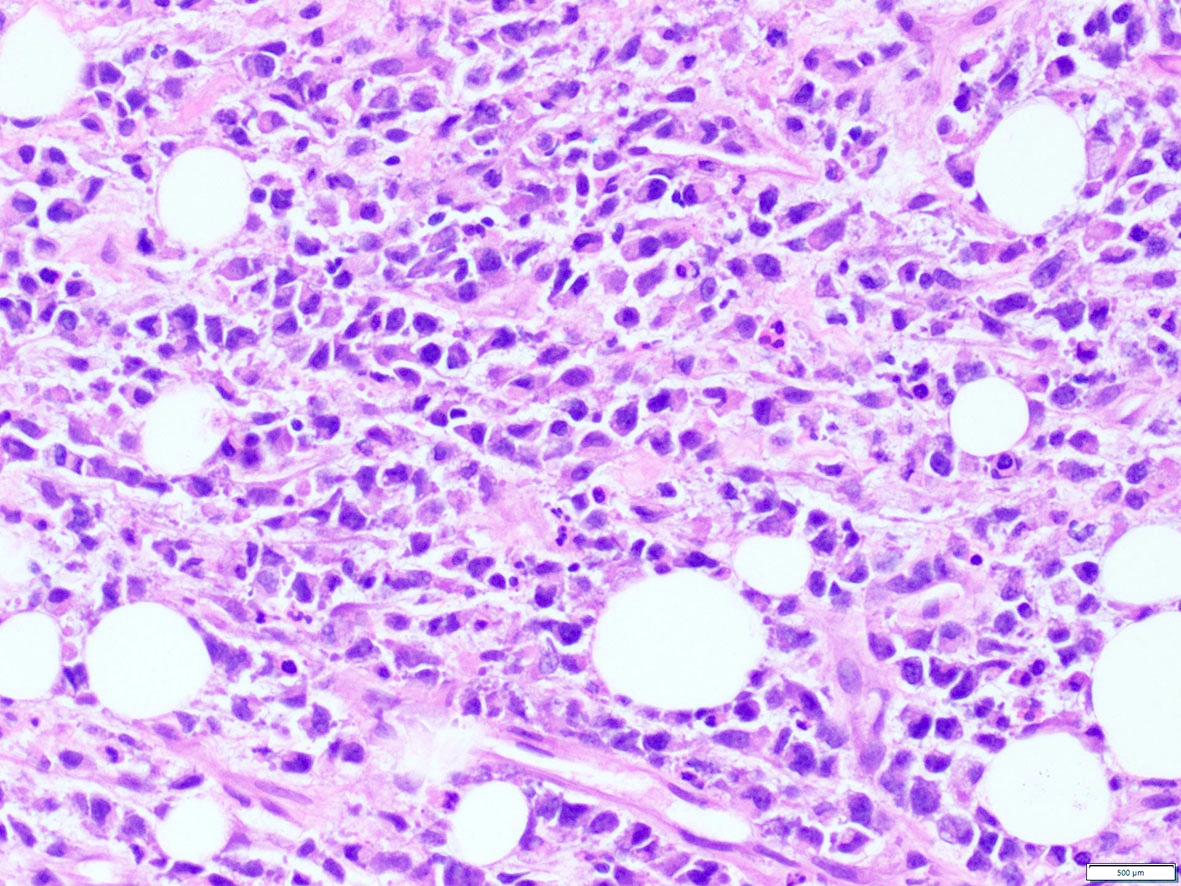

Microscopic (histologic) images

Contributed by A. Cristina Vargas, M.B.B.S., Ph.D., Patricia Guzman, M.D., Fiona Bonar, M.B.B.Ch., Alison Cheah, M.B.B.S. and Martin Jones, M.B.B.S.

Positive staining - disease

- ALK overexpression as a result of gene translocations / fusions:

- 50% of inflammatory myofibroblastic tumors (IMT) (Am J Surg Pathol 2015;39:957)

- Including the aggressive variant, epithelioid inflammatory myofibroblastic sarcoma (Am J Surg Pathol 2011;35:135)

| Inflammatory myofibroblastic tumor (IMT) | TPM3, TPM4, RANBP2, TFG, CARS, ATIC LMNA, PRKAR1A, CLTC, FN1, SEC31A, EML4, DCTN1, PPFIBP1, FN1 | Am J Surg Pathol 2015;39:957, Oncol Lett 2019;17:2020 |

| Epithelioid IMT | RANBP2 | Am J Surg Pathol 2011;35:135 |